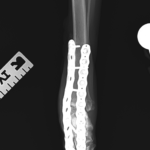

足根関節を適切な角度で固定し、関節面のバーリング、チタン製の2.7 ロッキングプレートをOrthoganal 方向で2枚用いて強固に固定し、早期の荷重を目指します。